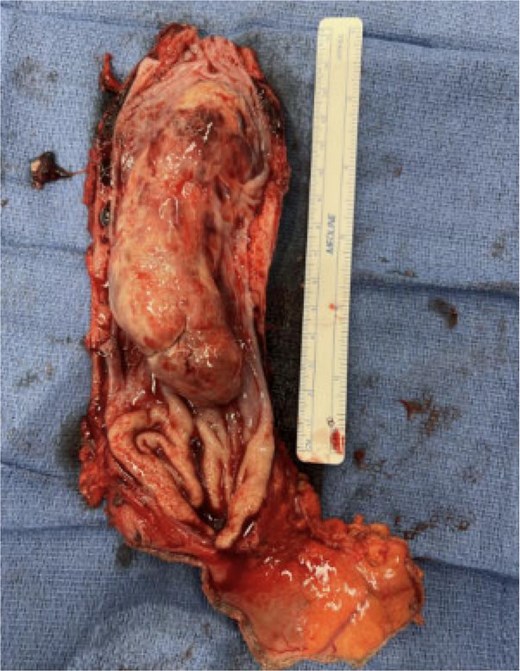

A multidisciplinary discussion was held and in the setting of the rapid tumor progression with biology favoring sarcoma and no evidence of distant disease, the decision was made to pursue upfront surgical resection rather than neoadjuvant therapy. The patient underwent a three field near total esophagectomy with an uneventful postoperative hospital course. A fluoroscopic esophagram was performed on postoperative day 6 without evidence of contrast extravasation (Fig. 4). The final pathology revealed an 8.7 cm high-grade pleomorphic rhabdomyosarcoma with mucosal and submucosal invasion, sparing the muscularis propria with 0/11 lymph node involvement (Fig. 5). This was formally graded as Stage IIIA (pT2N0M0), based on the soft tissue sarcoma criteria of AJCC.